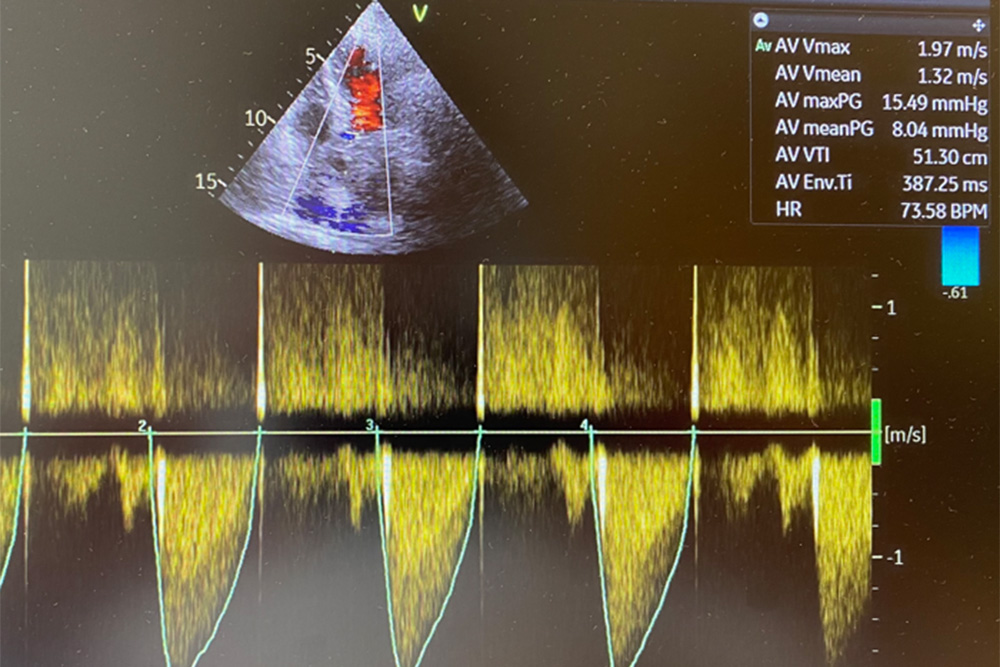

- Herzultraschall (Echokardiographie)